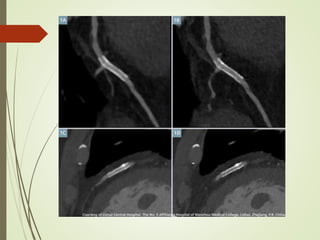

(A). CT- FFR in LAD was 0.72. Invasive coronary angiography and FFR

confirmed functionally significant stenosis. (B). CT-FFR demonstrates

no ischemia in LAD after virtual stenting, with computed value 0.86.

Invasive FFR after stent implantation 0.90

(A). CT- FFRin LAD was 0.72. Invasive coronary angiography and FFR confirmed functionally significant stenosis. (B). CT-FFR demonstrates no ischemia in LAD after virtual stenting, with computed value 0.86. Invasive FFR after stent implantation 0.90